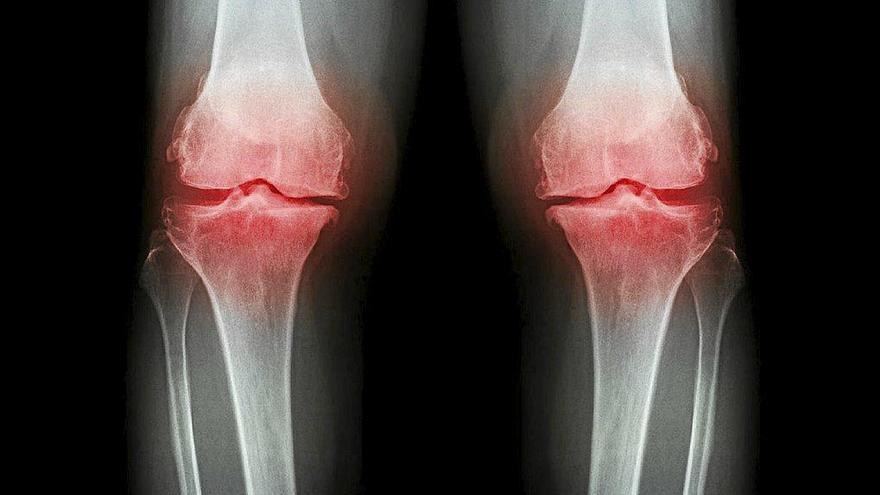

Osteoporosis: Cómo prevenir la epidemia silenciosa del siglo XXI

Ocho de cada 10 personas convive con la osteoporosis sin saberlo

a pérdida de densidad de los huesos puede provocar fracturas

Casi tres millones de personas padecen osteoporosis en el Estado, pero la mayoría desconoce el impacto que esta patología ósea, la más común del mundo, puede suponer a largo plazo. Conocida como la enfermedad silenciosa, la osteoporosis proviene de la insuficiencia de masa ósea y el deterioro estructural del tejido óseo, y no suele presentar síntomas hasta que la pérdida de densidad de los huesos es tan grave que suele acabar provocando una fractura. ¿Cómo prevenirla? ¿Qué opciones hay para tratarla? Nuestra doctora de cabecera Sonia Gárate ha abordado esta cuestión en su consulta radiofónica en Onda Vasca con Txema Gutiérrez.